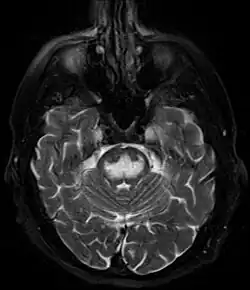

It can be diagnosed clinically in the appropriate context, but may be difficult to confirm radiologically using conventional imaging techniques. Changes are more prominent on MRI than on CT, but often take days or weeks after acute symptom onset to develop. Imaging by MRI typically demonstrates areas of hyperintensity on T2-weighted images.[30]